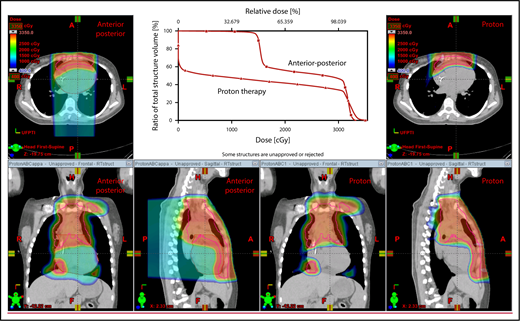

With regard to field arrangements, the PBSPT technique for an anterior upper mediastinal and lower neck target usually requires 1 (repainted) or 2 anterior fields. For more complex target volumes, targets can be divided into 2 or more parts (eg, neck CTV, mediastinal CTV, and axillary CTV), and a multifield plan can be used (Figure 5). For cases that involve lower (posterior) and upper (anterior) mediastinal targets, a combination of posterior and anterior fields can maximally spare the heart and lungs (Figure 6). For upper neck targets, lateral or posterior fields can avoid the oral cavity/salivary structures. For axillary targets, a posterior field can help to spare breast tissue. Although these various field arrangements can be used in PSPT, gradient matching is simpler in PBSPT when the fields overlap or oppose, obviating the need for feathering.

Plans for PBSPT with a single-field uniform dose and a gradient match, with anterior and posterior beams used to treat disease that involves the bilateral upper neck and the mediastinum (disease anterior to the right heart).